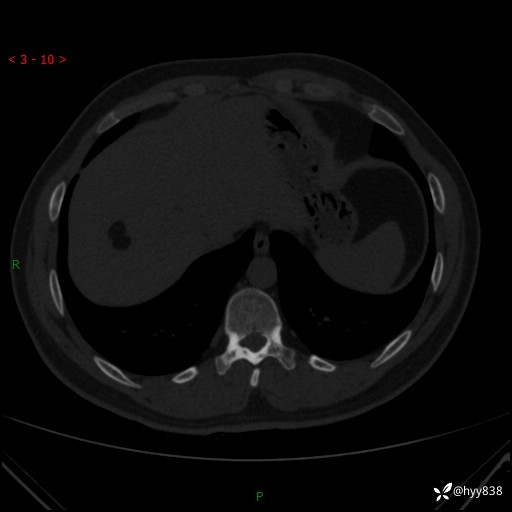

患者性别:男

患者年龄:28岁

简要病史:右肾肿瘤术后,常规复查

辅助检查:CT

临床诊断:右肾肿瘤术后

腹部CT+颅脑CT平扫